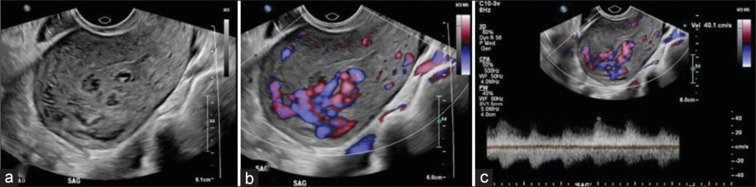

Postpregnancy bleeding is common after failed pregnancy, termination of pregnancy, and postnatally after both vaginal and cesarean delivery. Pelvic ultrasound (US) is usually the initial imaging modality of choice to ascertain the cause when the bleeding is heavy or prolonged. When used in combination with Doppler studies, US can help differentiate retained products of conception (RPOC) from rarer uterine vascular malformations (UVM), including true arterial vascular malformations and areas of enhanced endometrial vascularity (EMV), which may themselves be associated with any RPOC present. While the management of RPOC is well established and has evolved from an almost universal surgical approach to increasingly more medical or expectant alternatives, clinical decisions over the management of a concurrent UVM are less clear and treatment options need to be individualized depending on features of the lesion and the clinical situation with hysteroscopy featured as an important modality, especially when dealing with EMV's. In this review, we discuss the role of hysteroscopy in the treatment of enhanced myometrial vascularity with and without associated RPOC and propose a management algorithm.